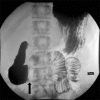

Background: Superior mesenteric artery (SMA) syndrome is an uncommon condition resulting in partial small bowel obstruction because of external compression of the third portion of the duodenum between the SMA anteriorly and the aorta posteriorly. SMA syndrome often presents with postprandial nausea, bilious vomiting, and abdominal pain with associated weight loss. Onset of symptoms can be acute (occurring in the setting of rapid weight loss because of trauma/surgery) or can be vague and chronic over many years.

Case reports: We present two cases of female adolescents who presented with symptoms of duodenal obstruction attributed to SMA syndrome. Both failed conservative treatment with weight gain and underwent successful laparoscopic duodenojejunostomy procedures with resolution of duodenal obstruction.

Conclusion: In the differential diagnosis of persistent nausea and bilious vomiting, even in the setting of an eating disorder, SMA syndrome should be considered. Upper gastrointestinal examination is the primary modality for diagnosing SMA syndrome, but ultrasound is an inexpensive, rapid screening tool for patients with unexplained abdominal pain. Abdominal computed tomography may also be helpful in selected patients. Conservative therapy consisting of nutritional support to enhance weight gain is usually sufficient and is accomplished with placement of a nasojejunal feeding tube past the point of duodenal compression. When conservative therapy fails, laparoscopic duodenojejunostomy can provide definitive relief of the obstruction.